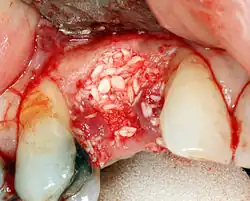

To achieve an adequate width and height of bone, various bone grafting techniques have been developed. The most frequently used is called guided bone graft augmentation where a defect is filled with either natural (harvested or autograft) bone or allograft (donor bone or synthetic bone substitute), covered with a semi-permeable membrane and allowed to heal. During the healing phase, natural bone replaces the graft, forming a new bony base for the implant.[56]: 223

Additional procedures to augment deficient bone in implant site

For an implant to osseointegrate, it needs to be surrounded by a healthy quantity of bone. In order for it to survive long-term, it needs to have a thick healthy soft tissue (gingiva) envelope around it. It is common for either the bone or soft tissue to be so deficient that the surgeon needs to reconstruct it either before or during implant placement.[50]: 1084 All techniques of augmenting the alveolar bone in preparation for implant placement are invasive and associated with a degree of morbidity.[59]

Hard tissue (bone) reconstruction

Bone grafting is necessary when there is a lack of bone. It also helps to stabilize the implant by increasing survival rates of the implant and decreasing marginal bone level loss.[60] While there are always new implant types, such as short implants, and techniques to allow compromise, a general treatment goal is to have a minimum of 10 mm (0.39 in) in bone height, and 6 mm (0.24 in) in width. Alternatively, bone defects are graded from A to D (A=10+ mm of bone, B=7–9 mm, C=4–6 mm and D=0–3 mm) where an implant's likelihood of osseointegrating is related to the grade of bone.[61]: 250